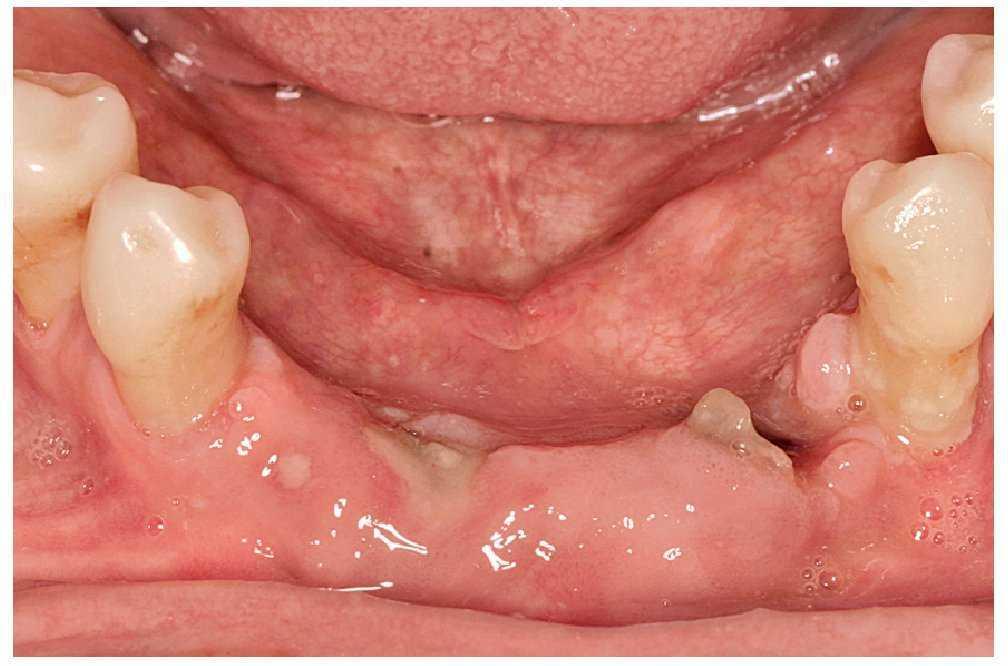

Las necrosis maxilares y mandibulares se caracterizan por la aparición de zonas óseas expuestas como resultado de intervenciones odontológicas o debido a microlesiones. Es frecuente que después de extracciones dentarias se genere una herida tórpida que no cicatriza, con zonas óseas expuestas, no cubiertas ni por mucosa ni por un coágulo sanguíneo. Estas zonas óseas presentan una coloración amarillenta-grisácea y la mucosa adyacente está eritematosa (fig. 3). A diferencia de una alteración de la cicatrización normal, este cuadro puede acompañarse inicialmente de poco dolor, pero en una fase más avanzada el paciente puede sufrir un dolor intenso en esta zona. Además, llama la atención una halitosis marcada, lo que afecta aún más al paciente.

Figura 3. Hueso expuesto y tumefacción de la mucosa adyacente a la osteonecrosis.

A esto se pueden añadir diferentes grados de movilidad dentaria, trastornos de la sensibilidad sobre todo en el área del mentón y del labio inferior, y también fístulas. En casos de afectación extensa pueden aparecer trayectos fistulosos extraorales (figs. 4a a 4c).

Figura 4a. Osteonecrosis muy marcada con áreas extensas de hueso expuesto, fístulas múltiples y tumefacciones mucosas.